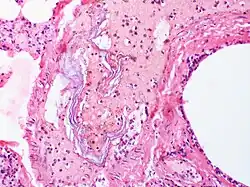

Intravascular squames are present in this example of amniotic fluid embolism. | |